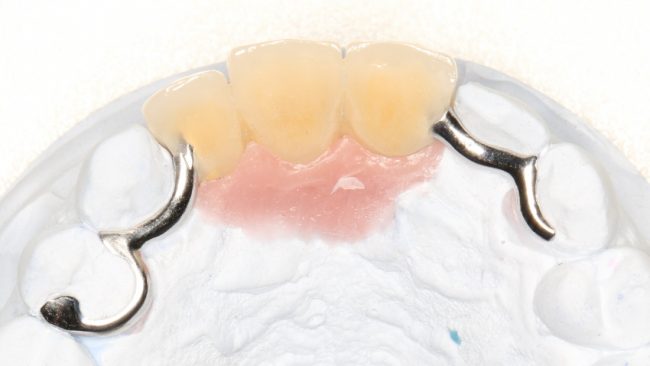

Рекомендации по установке имплантов. Для всех. Часть V.